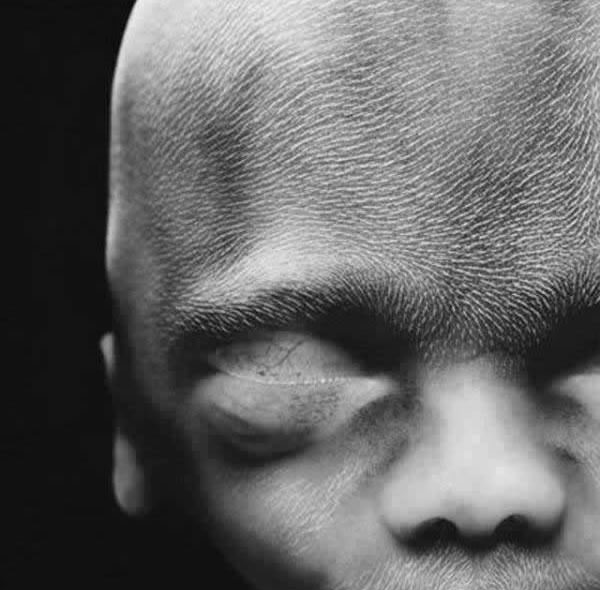

16. hét

A csont mégcsak porc, de látszik az érrendszer